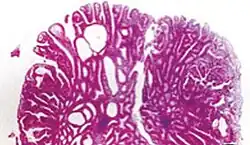

Tubular adenoma 2% at 1.5 cm[12] Low to high grade dysplasia[13] Over 75% of volume has tubular appearance.[14]

Tubulovillous adenoma 20% to 25%[15] 25–75% villous[14]

Villous adenoma 15%[16] to 40%[15] Over 75% villous[14]